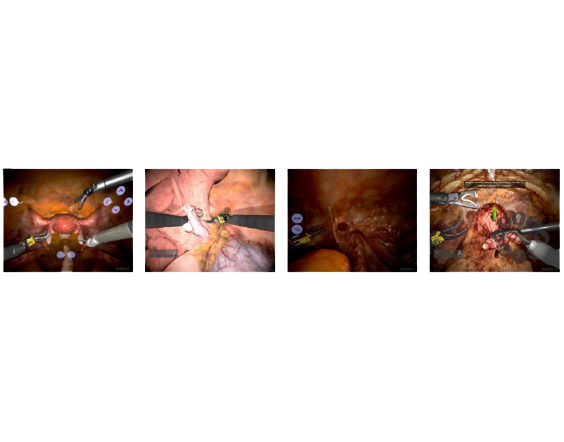

O da Vinci SimNow é um software com serviço all-inclusive para programas de simulação robótica e aprendizado do uso da tecnologia da Vinci. Desenvolvido para ser usado com o console do cirurgião, ele é bastante realista ao simular a cirurgia robótica usando os controles e visor 3D HD do próprio sistema da Vinci. Ao disponibilizar exercícios com conteúdo especializado, ele possibilita aprimorar habilidades em todas as etapas de desenvolvimento do cirurgião robótico.

A plataforma permite simulação padronizada compatível com todos os sistemas da Vinci (Si, Xi e X), updates automáticos de software, gerenciamento remoto e online da performance dos usuários e manutenção constante facilmente acessível. O simulador possui biblioteca extensa de exercícios, com desenvolvimento constante de novos módulos e novas atividades para treinamento de habilidades e de cirurgias.